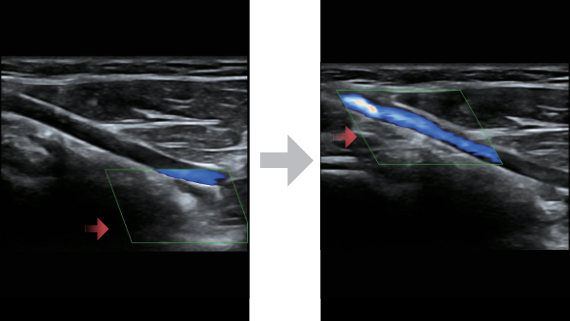

Sobre la base de un profundo conocimiento de las necesidades del cliente, el DC-60?ECHO con X-Insight estå dise?ado para brindar alta eficiencia con imågenes precisas, lo que se ve potenciado con eXpress Clarity (claridad exprés), eXceptional Intelligence (inteligencia excepcional) y eXceeding Experience (experiencia extraordinaria).

eXceeding Experience

Experiencia con alta productividad